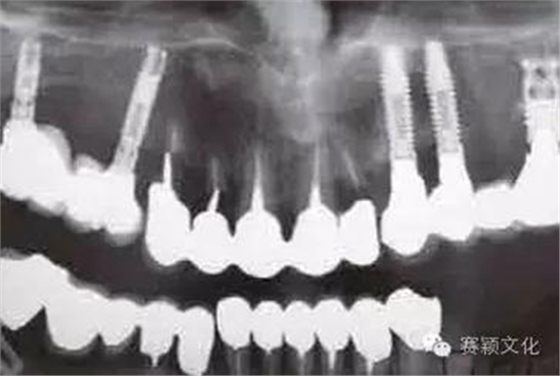

圖2 術(shù)前全景片

在某些特殊情況下,種植體需植入類骨質(zhì)(例如含BMP-2移植骨材料,密質(zhì)骨<15%)中,此時最好使用表面處理且粗糙的種植體。此處展示一應(yīng)用粗糙且表面處理的螺紋型種植體行拔牙位點的即刻種植(圖2~8)